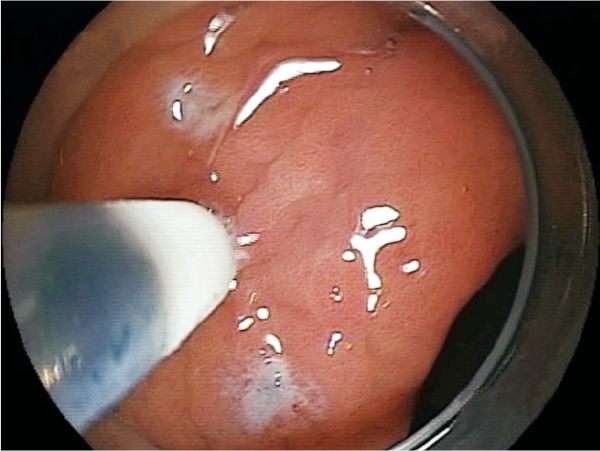

Makes clear marking around the lesion.

Washes off lesion tissue adhering to the tip as needed.